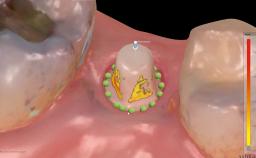

In this case, immediate implant placement and an immediate provisional prosthetic reconstruction (type 1A) were performed by Stefan Röhling and Thomas Borer to reduce the treatment time and to provide the patient with a fixed implant-supported prosthetic reconstruction directly after implant placement.

Tooth 31 had been immediately re-implanted but not endodontically treated, resulting in external root resorption. Later, the tooth did receive endodontic treatment; the apical part of the root was resected, and the crown was stabilized with composite and attached to the neighboring teeth with a wire.